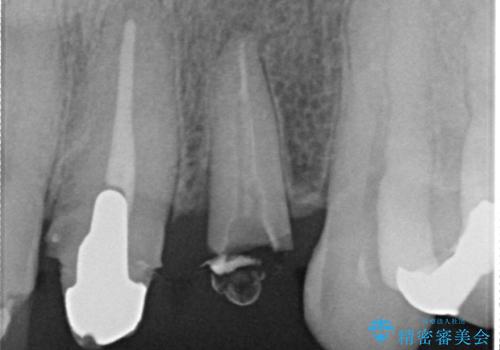

左上1、2番目の歯は仮歯の状態だったので外して状態を確認したところ、左上2は垂直的な歯根破折を認めたため抜歯となりました。左上1は再根管治療を行いました。

左上2抜歯後、骨および歯肉の回復を待ち、オールセラミッククラウンのブリッジによる欠損補綴を行いました。